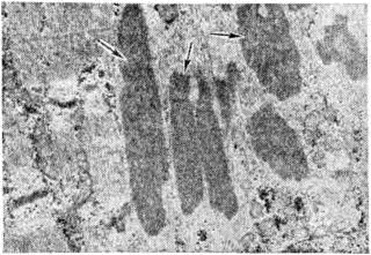

Наиболее ранние ультраструктурные изменения в мышцах при Миопатия характеризуются утолщением и расщеплением Z-линий с последующим разрушением миофибрилл мышечного волокна. Благодаря фазово-контрастной и электронной микроскопии выявлены дефекты в мембранных системах мышечного волокна. Гистоферментохимически отмечается ослабление реципрокных отношений между гликолитическими и окислительными ферментами в мышечных волокнах различного типа.

Болезнь центрального стержня, гистологически характеризующаяся присутствием в мышечных волокнах центральных участков, которые окрашиваются эозином интенсивнее, чем остальная саркоплазма, лишены гликогена и ферментативной активности. Электронно-микроскопически стержень представлен аморфными и неправильно расположенными фрагментами миофиламентов и Z-линий, митохондрии и саркоплазматический ретикулум отсутствуют.

Немалиновая Миопатия, характеризующаяся наличием в субсарколеммных зонах части мышечных волокон нитевидных структур (рисунок 7). Гистохимически в них выявлены рибонуклеопротеиды и высокая активность тирозиназы.

5. Митохондриальные миопатии — группа врождённых медленно прогрессирующих заболеваний, при которых основные изменения в мышечной ткани связаны с аномалиями митохондрий. Среди заболеваний этой группы выделяют: 1) плеокониальную Миопатия, характеризующуюся тем, что митохондрии мышечных волокон содержат множественные кристы и иногда круглые осмиофильные включения; 2) мегакониальную Миопатия, характеризующуюся присутствием в мышечных волокнах скоплений увеличенных причудливой формы митохондрий, которые могут содержать необычные включения; 3) митохондриальную Миопатия с гиперметаболизмом, характеризующуюся присутствием в перинуклеарных участках мышечной клетки гигантских митохондрий, которые могут быть трёх типов: 1-й тип — с тубулярным типом крист, 2-й тип — с непрозрачными тельцами, 3-й тип— состоящие из плотных концентрических тяжей. Гистохимически в мышцах выявляется высокая активность окислительно восстановительных ферментов.